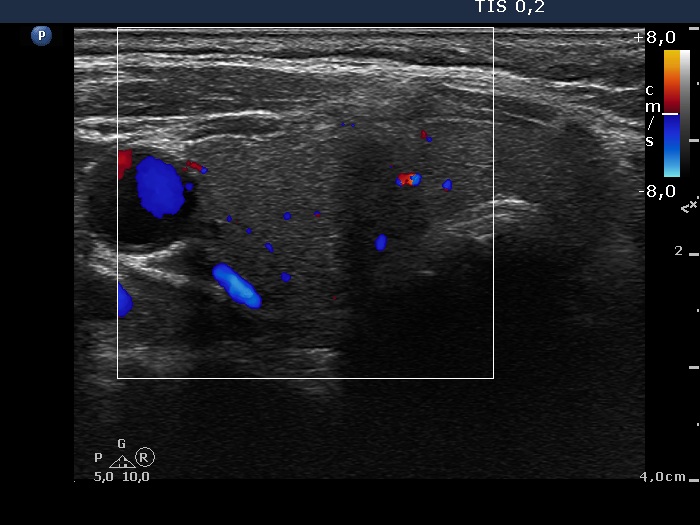

Ultrasonography: the right thyroid was echonormal while the left lobe contained moderately hypoechogenic areas with a 50% echogenicity index. There was a hypoechogenic mass lower and lateral to the right thyroid. The lesion did not present a regular hilum.